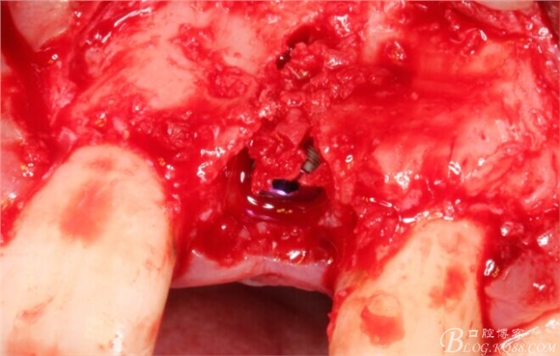

旋入一長(zhǎng)兩短3顆鈦釘。

將自體骨與BIO-OOS骨粉混合植到術(shù)區(qū),蓋生物膜。

縫合。